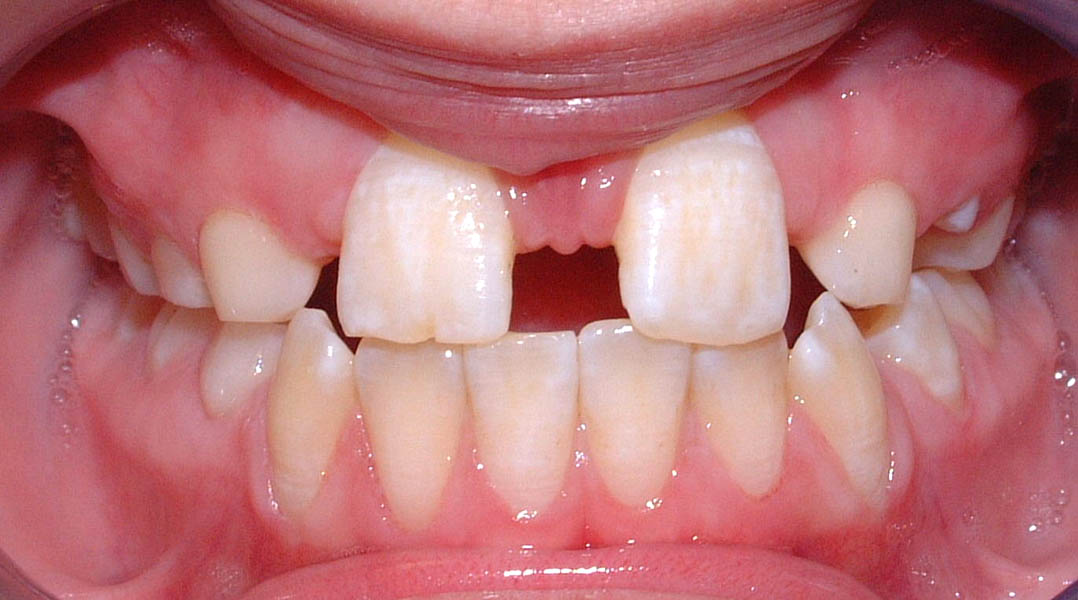

La momentul prezentării în clinică, în decembrie 2002, pacienta avea 8 ani şi o lună şi suferea de fibroză chistică şi de o deficienţă de dezvoltare a etajului mijlociu al feţei. Aceasta prezenta o anomalie de clasa I care mima o anomalie de clasa a III-a. Incisivii centrali, laterali şi caninii temporari maxilari, precum şi molarii prim şi secund de pe partea stângă erau în ocluzie inversă. În plus, pacienta prezenta coloraţii ale dinţilor de etiologie idiopatică (fig. 1). Autorii au considerat coloraţiile ca fiind de suprafaţă, extrinsece şi nu determinate de fibroza chistică, dovadă îndepărtarea acestora prin periaj profesional. Radiografia panoramică efectuată cu 6 luni înainte de prezentarea în clinica stomatologică relevă anodonţia incisivilor laterali superiori şi a premolarului secund drept inferior, ca şi posibila incluzie a caninilor maxilari, în special a celui stâng (fig. 2).

A doua etapă a tratamentului a fost amânată până în aprilie 2006, când pacienta a împlinit vârsta de 11 ani şi 5 luni. În acel moment, fetiţa prezenta erupţie şi dezvoltare radiculară adecvată, astfel că aparatele fixe aplicate acum n-ar fi purtate o perioadă îndelungată. Ocluzia inversă frontală şi angrenajul invers lateral fuseseră corectate; totuşi, exista o diastemă mare, în principal cauzată de lipsa incisivilor laterali superiori (fig.3). În acest moment, radiografia panoramică relevă anodonţia incisivilor laterali maxilari şi a premolarului secund drept mandibular, o anatomie redusă a rădăcinilor incisivilor centrali superiori, incluzia caninului superior stâng şi dezvoltarea întârziată a rădăcinii celui de-al doilea premolar inferior (fig. 4).